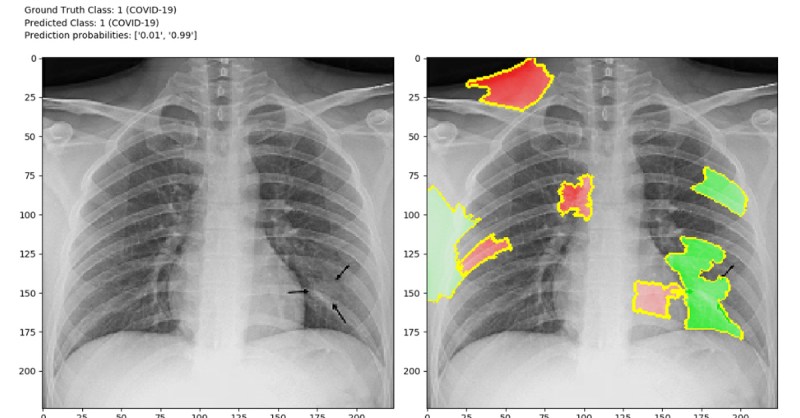

नई AI प्रणाली, जो कि "साइंटिफिक रिपोर्ट्स" जर्नल में प्रकाशित एक पेपर में विस्तृत है, एक गहन शिक्षण-आधारित एल्गोरिद्म का उपयोग करती है जिसे कस्टम कनवोल्यूशनल न्यूरल नेटवर्क (कस्टम-CNN) कहा जाता है। यह एल्गोरिदम एक्स-रे छवियों में कोविड-19 के मामलों, सामान्य मामलों और निमोनिया के बीच जल्दी और सटीक रूप से अंतर करने में सक्षम है।

प्रोफेसर गंदोमी ने कहा, "गहन शिक्षण एक एंड-टू-एंड समाधान प्रदान करता है, जिससे बायोमार्करों की मैन्युअल खोज की आवश्यकता समाप्त हो जाती है। कस्टम-CNN मॉडल पता लगाने की प्रक्रिया को सुव्यवस्थित करता है, जिससे कोविड-19 का तेज और अधिक सटीक निदान किया जा सकता है।"

कस्टम-CNN मॉडल का मूल्यांकन एक व्यापक तुलनात्मक विश्लेषण के माध्यम से किया गया था, जिसमें प्रदर्शन मानदंड के रूप में सटीकता का उपयोग किया गया था। टीम ने बताया कि परिणामों से पता चलता है कि नया मॉडल अन्य AI डायग्नोस्टिक मॉडल से बेहतर